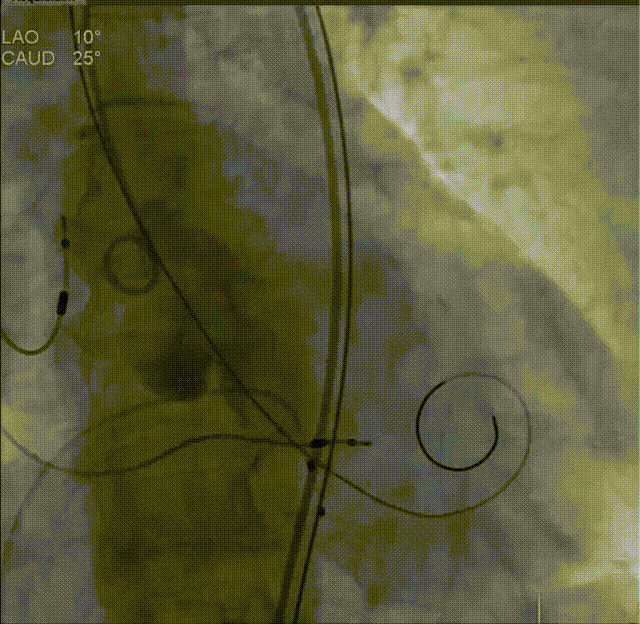

根部造影,导管测压70mmHg

球囊预扩,无腰征,无漏,考虑常规sizing,选用29mm THV